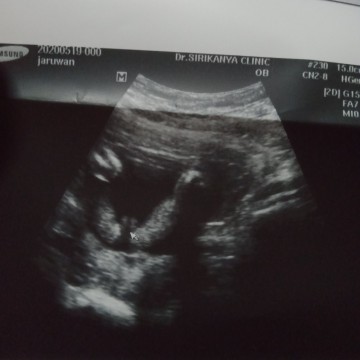

เพศอะไร

แม่ๆช่วยดูให้แน่ใจหน่อยได้ใหมคะว่าเพศชายหรือเพศหญิง

เราว่าผู้หญิงค่ะ เพราะเป็นแคมน้อง ถ้าผู้ชายต้องมีจู๋ เราก็ได้ลูกสาวหมอก็บอกว่าเป็นแคมน้อง แต่ของเราน้องนอนหนีบขา แต่ของแม่น้องอ้าขาให้ดูเลยจ้า555

ของเราแบบนี้ หมอบอกว่าผู้หญิงนะคะ เป็นกลีบจิ๋ม ไม่ใช่ไข่ค่ะแม่ ถ้าผู้ชายจะมีจู๋ยื่นออกมา ตอนแรกก็งง คิดว่าไข่ แต่หมอคอมเฟิมว่า เพศหญิงค่ะ

กี่สัปดาห์แล้วคะ ถ้าแน่ใจว่าน้องเพศไหน อัพเดทให้ฟังหน่อยนะคะ อยากรู้ค่ะ ส่วนตัวคิดว่าผู้หญิงนะคะ

แม่ๆจ๋า ขอบคุณสำหรับทุกๆคอมเม้นนะคะ วันนี้คุณหมอคอนเฟิร์มแล้วว่าน้องเป็นเพศหญิงนะคะ

รูปร่างเหมือนผู้หญิงค่ะ แต่มันใหญ่มาก โผล่ออกมาเยอะจนเหมือนของผู้ชายเลยจ้าแม่

เหมือนจะเพศชายนะคะ คล้าย ๆ ภาพที่หมอให้บ้านนี้ดูเลยค่ะ

เป็นพวงค่ะน่าจะเป็นผู้ชายนะคะแต่ไม่ร้อยนะคะ

ไม่แนใจว่าไข่หรือกลีบ รอดูครั้งหน้าดีกว่านะคะ

เหมือนผช.เลยค่ะแม่ ครั้งหน้าลองซาวน์อีกทีนะคะ